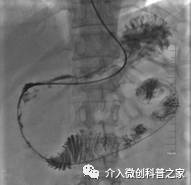

中晚期胰腺癌的供血动脉化疗药物灌注术

(高浓度药物靶向灌注杀死癌细胞)